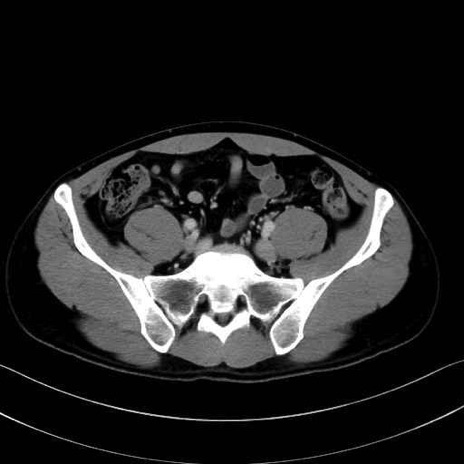

梨状筋(piriformis muscle) のCT画像の解剖

梨状筋 (Piriformis)